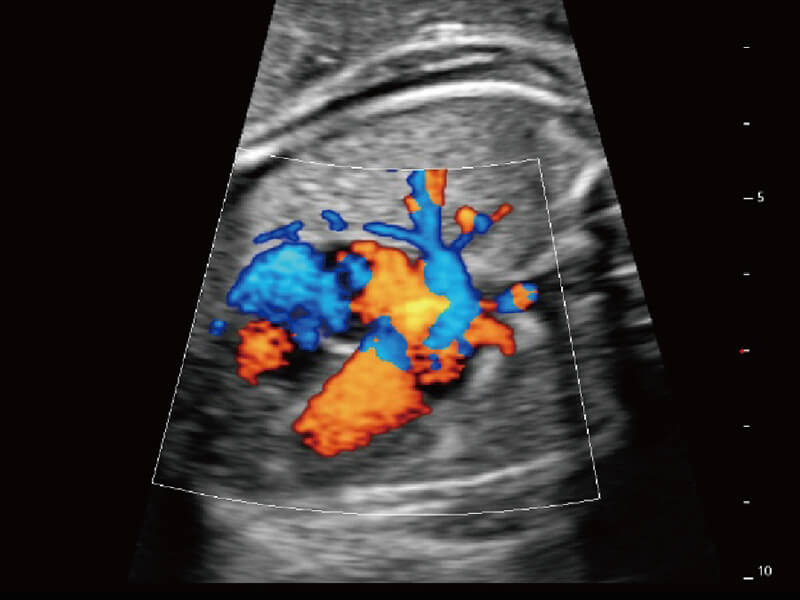

彩色多普勒超声诊断系统

S60探头工艺,从前端信号处理每一个环节采集无损声学数据,真实还原组织原貌,再现解剖细节。